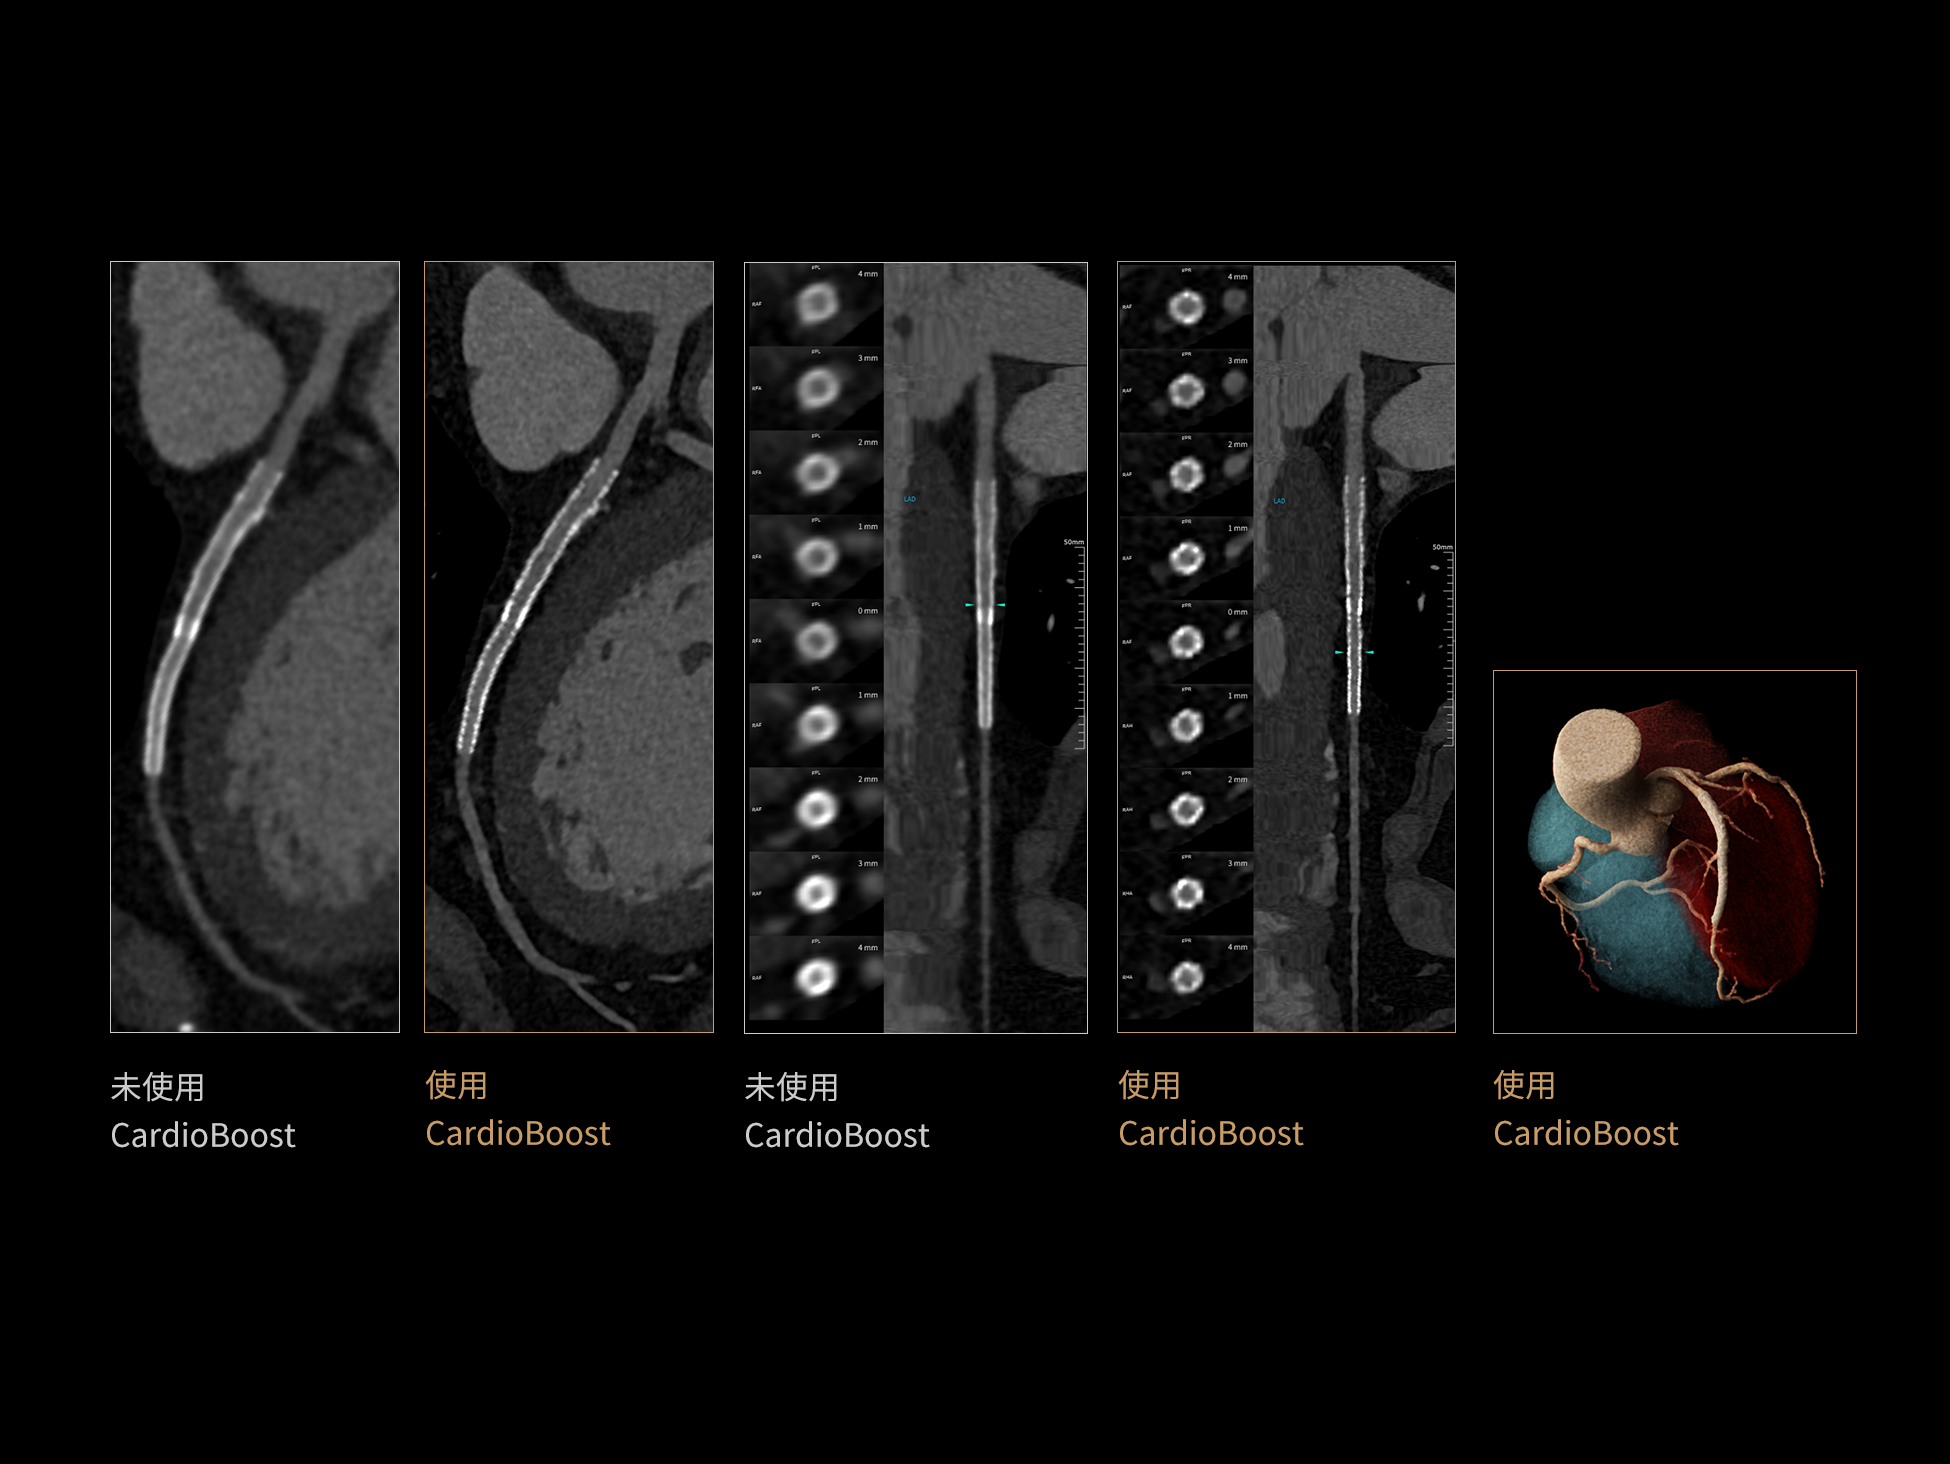

借助 3D 神经网络设计、空间注意力机制聚焦与特征强化作用,CardioBoost技术提升图像的空间分辨率,实现冠脉支架的高清成像,对支架形态与管腔通畅度的评估更精准。

CardioCapture:AI冠脉运动追焦技术

CardioCapture 算法在冠脉运动伪影校正中采用全局化、系统化的处理策略。以目标时相为核心,重建多个相邻时相图像,利用深度学习技术提取连续时相中的冠脉树结构,构建时相间的运动模型,并对分段重建图像进行精准校正。通过这一过程,CardioCapture 可实现等效21 ms的超高时间分辨率,大幅提升冠脉图像清晰度与判读可靠性。

传统的血管提取通常基于CT值阈值和固定的冠状动脉模型,这种方法常常会失效,尤其是对于存在运动伪影的血管。 CardioCapture 算法基于深度学习网络,充分学习各类冠脉图像,以适应不同冠脉场景,精准高效完成冠脉及中心线提取,相较于仅基于CT 值和固定解剖模型的传统算法,CardioCapture 对于小血管及末端血管显示优势更加显著。

冠脉运动伪影校正过程

有效提取冠脉分支